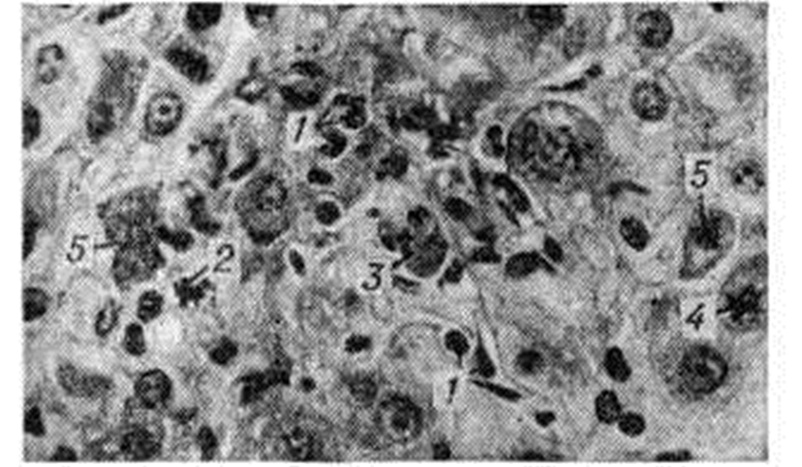

Рис. 8.

Микропрепарат печени при остром вирусном гепатите (пункционная биопсия): обратное развитие дистрофических изменений гепатоцитов; формирование «поздних» узелков (указано стрелкой) с сохранившимся коагуляционным некрозом гепатоцитов (а) и без коагуляционного некроза гепатоцитов (б); окраска гематоксилин-эозином; × 760.

Рис. 9.

Микропрепарат печени при безжелтушной форме острого вирусного гепатита (пункционная биопсия): обильные инфильтраты (указаны стрелками) в области центральной вены дольки печени (верхний рисунок) и в области портального тракта (нижний рисунок); окраска гематоксилинэозином; × 300.